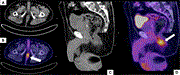

Treatment of metastatic carotid body paraganglioma in a young female

Aldin Malkoc and others

Journal of Surgical Case Reports, Volume 2025, Issue 1, January 2025, rjae811, https://doi.org/10.1093/jscr/rjae811

Curative resection of multiple primary neuroendocrine tumors enabled by preoperative imaging: a case report

Hidetoshi Shidahara and others

Journal of Surgical Case Reports, Volume 2025, Issue 1, January 2025, rjae805, https://doi.org/10.1093/jscr/rjae805